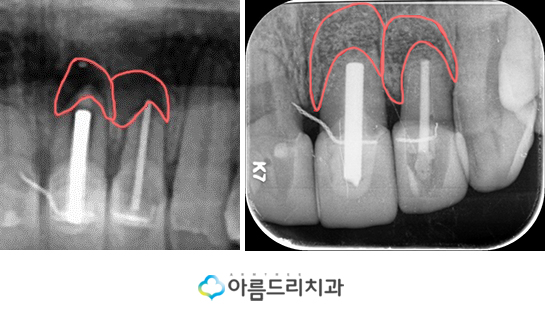

좌측에 있는 사진이 치료를 하기 전 사진

으로 잇몸의 염증으로 인하여 X-ray상

검은 부분을 확인할 수 있지만 우측의

사진을 보시면 염증으로 인해 검게

보였던 부분이 다시 하얗게 주변의

정상적인 잇몸으로 다시 변화한

것을 확인해보실 수 있을 것입니다.